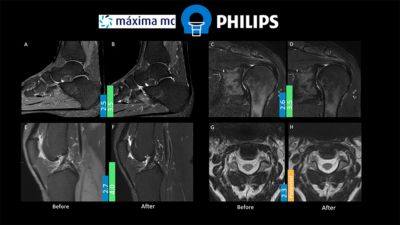

As part of the qualitative survey, the areas of image quality improvement were identified. Those were confirmed during interviews and image review sessions with radiologists.

After the training event, Philips delivered a report to the radiologists and MR coordinator during their weekly radiologists meeting “Heilig uur.” Image optimization results were shared, and validation of the new protocols was planned.

The Máxima MC team tested the protocols in the clinical environment. Twelve new protocols were implemented on two 1.5T MR scanners. Six optimized protocols were implemented on the 3.0T system.

To evaluate the optimized protocols, a 5-point scale was created to assess signal-to-noise, contrast-to-noise, sharpness/resolution and artifact level. The radiologist reviewed several patient cases before and after optimization and scored the image quality. The average scores are displayed in figure 1.